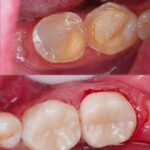

Dental Treatment Before and AfterClick To Enlarge White Teeth Lips Closeup Teeth Whitening Before After Teeth Whitening Transformation Before After Teeth Transformation Before After Man White Teeth Mustache Smile Teeth Whitening Transformation Before After Teeth Before After Transformation Teeth Before After Treatment Teeth Before After Composite Bonding Teeth Whitening Transformation Before After dental treatment dental treatment dental treatment dental treatment dental treatment dental treatment dental treatment dental treatment dental treatment dental treatment dental treatment dental treatment dental treatment dental treatment dental treatment dental treatment dental treatment dental treatment dental treatment